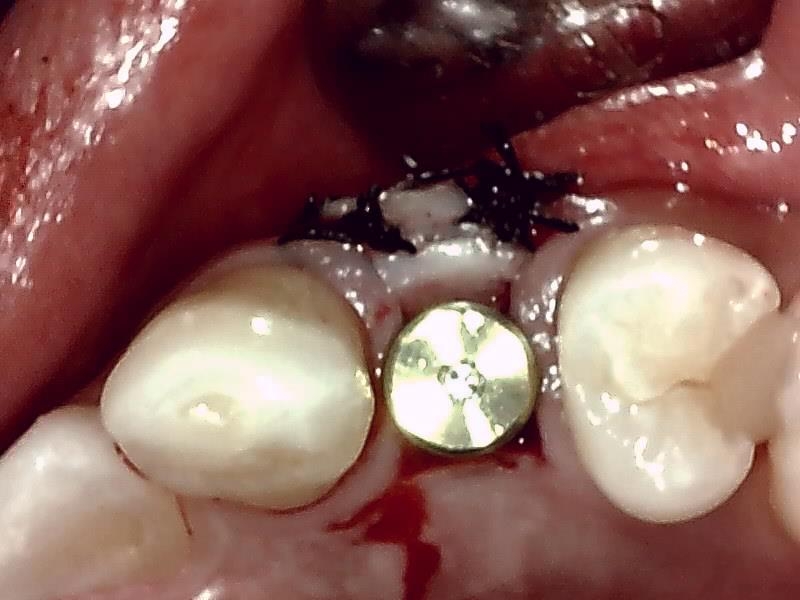

インプラント体の埋入

ヒーリングアバットメント装着

骨造成 自家骨移植

縫合